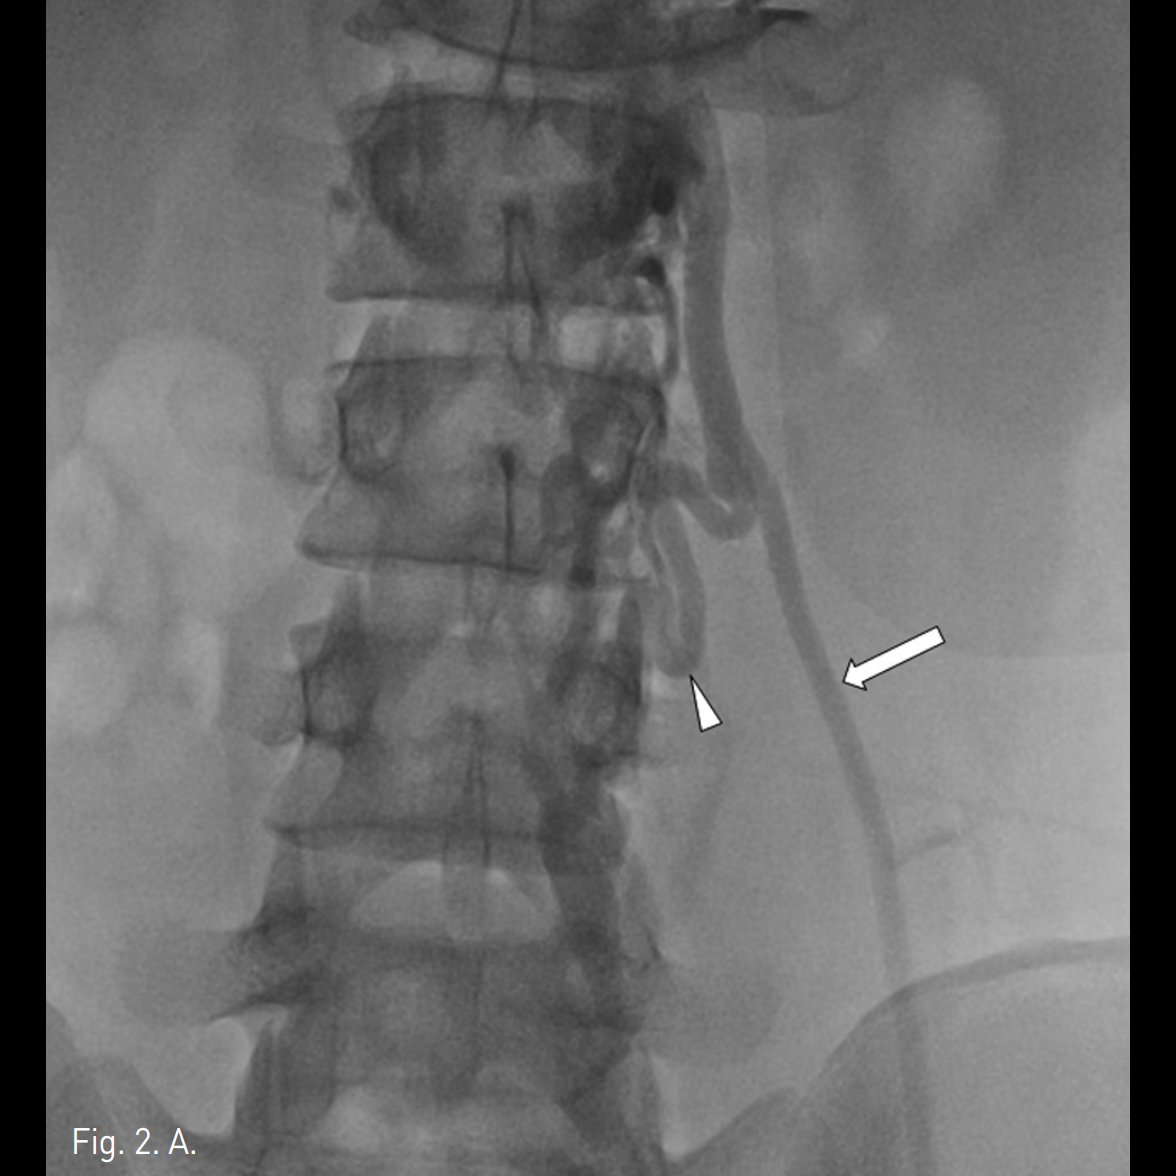

우측 상박을 tourniquet으로 묶은 후 초음파 유도 하에 우측 basilic vein을 minipuncture set을 이용해 천자하여 4Fr Cobra catheter (100cm)를 좌측 신정맥에 위치시킨 후 table tilting을 하여 조영제를 넣었을 때 좌측 spermatic vein.으로의 역류가 관찰되며 L3 level에서 retroperitoneum으로 통하는 venous tributary가 있으며 main tributary는 좌측 pampiniform plexus로 역류되는 소견이 보임(Fig. 2A, 2B). Microcatheter (Renegade, Boston Scientific, Watertown, MA)를 이용하여 보다 자세한 정맥조영을 얻었을 때 inguinal canal level에서 두 개의 정맥이 관찰됨(Fig. 2C). Subinguinal level에서 3개의 microcils (2~3mm ; micronester, Cook, Bloomington, IN)를 이용하여 색전술을 시행하였음 (Fig. 2D). 이어서 환자의 왼쪽 손가락을 이용해 inguinal level을 압박하게 하고 조영제를 주입했을 때 고환으로의 조영제 흐름이 차단된 것을 확인한 후(Fig. 2E), foam sclerotherapy (2mL of 3% STS [sodium tetradecyl sulfate, Thrombojet] + 3mL of air) 5mL를 Cobra catheter를 통해 시행함. 근위부 spermatic vein에 3개의 coils (6mm Nester coils)로 색전술을 시행함. 최종 좌측 신정맥조영술에서 spermatic vein이 조영되지 않음(Fig. 2F).

Fig. 2

A, B. Left renal venograms (via right brachial approach) show confluence of the left spermatic vein (arrow in 2A) presenting an incompetent valve and reflux of contrast medium into an ectatic pampiniform plexus (arrow in 2B). Another tributary (arrowhead in 2A) to the retroperitoneum is seen.